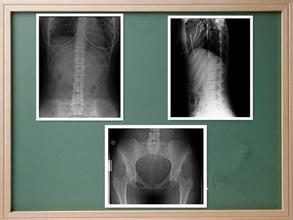

、随着强直性脊柱炎的病情逐渐进展,患者慢慢的就会出现比较明显的坐骨神经痛,有的时候会是左右臀部交替疼痛,还有的患者则会出现腰背疼痛,这种情况在 患者做X线片上,可以看出多数的患者的骶髋关节会出同一些病变,所以对于强直性脊柱炎患者来说骶髋关节会有疼痛也是比较明显的一种症状了。